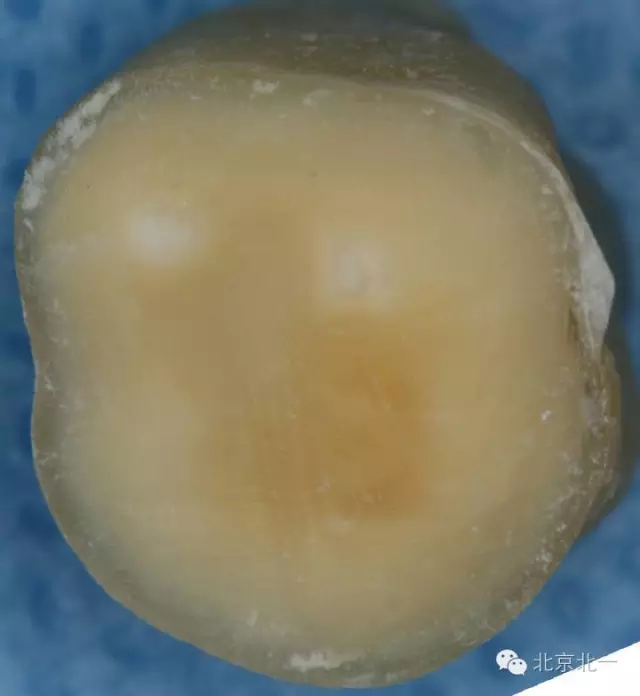

這只是因為學生們對于牙體組織的顏色沒有很好的理解,髓頂?shù)纳珴膳c其下方髓底的顏色有著顯著的不同(下圖為同一顆牙不同層面的片切圖 A為髓頂與穿髓孔B為下方的髓底與根管口)。